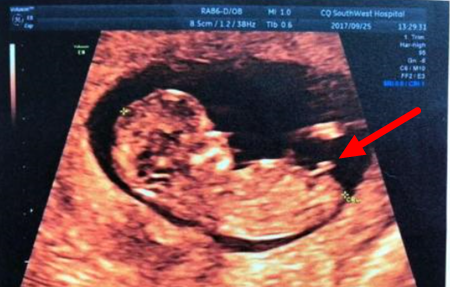

(NT男宝图,nub特征点)

如果NT是只做局部那是看不出来的,医生会有超全景图,就能分辨性别,因为区分的方法主要是依靠宝宝的第二性征点,简单来说NT检查的时候宝宝的第二性征还没发育好,但是已经可以初见雏形,这时候家长就可以通过NT单子的宝宝特征点来区分男女了。

男孩的特征点与身体呈45度角,还多一些,而女孩儿的特征点几乎和躯体平行。还有就是如果是男宝宝,屁股位置会微微上翘,后背脊柱成圆弧状,因为要留空间发育前列腺,相反,女宝宝后背脊柱就相对就平一些。